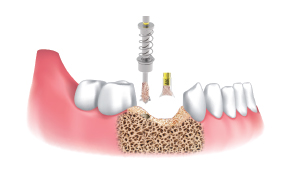

Utilizar fresa final (igual o mayor a Ø3.5/4.0) de acuerdo al protocolo de fresado del fabricante y al plan de tratamiento.

Instalar implante.

Aplicar las limallas de hueso obtenidas en el sitio de regenaración.

Luego de la instalación del implante, se conectan los pilares de cicatrización y se lleva a cabo la regeneración ósea en el defecto.